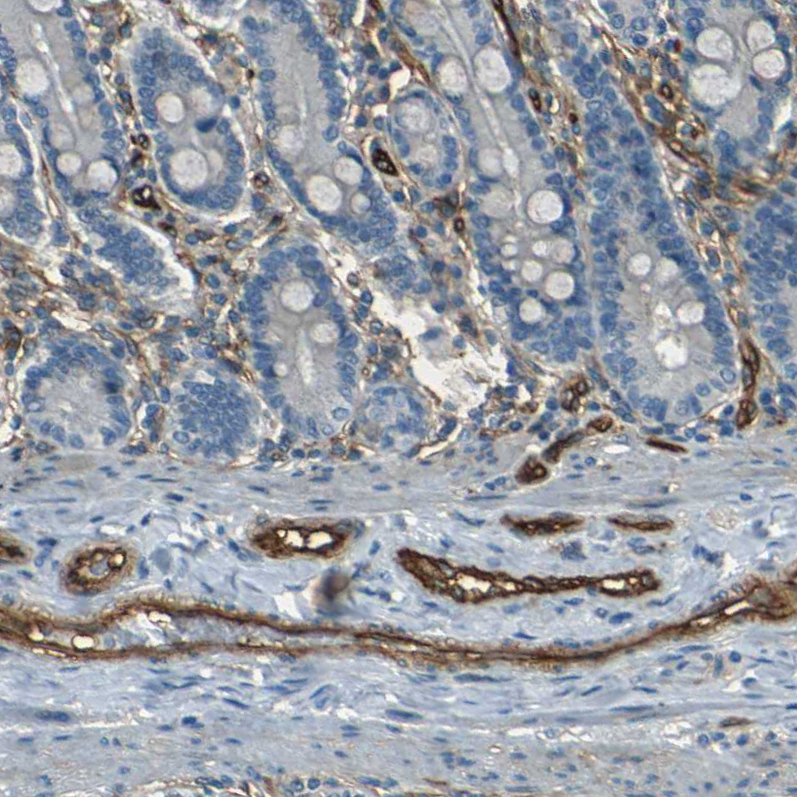

Immunohistochemistry analysis in human placenta and skeletal muscle tissues using HPA014067 antibody. Corresponding ENTPD1 RNA-seq data are presented for the same tissues.